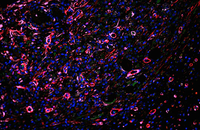

- Confirmation of the nature of differentiated cells by ICC method

- Investigation of cell placement on tissue scaffold